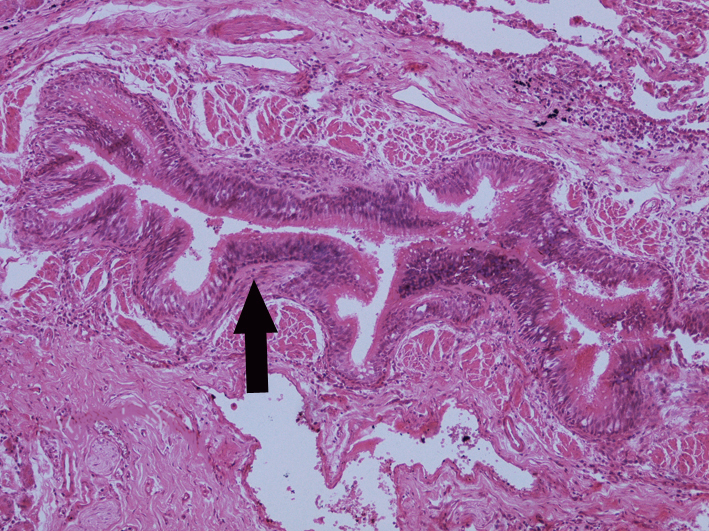

4.Bronchiectasis